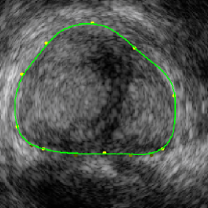

This measure requires less data to achieve statistical power compared to the two-dimensional Pearson correlation, but it is more general than the identity-assuming SSD with its zero DOF. It is invariant to low-frequency intensity shifts between the compared images, which is why we called it shift correlation 𝒟SCsubscript𝒟𝑆𝐶\mathcal{D}_{SC}. The invariant frequency range is controlled by the standard deviation σ𝜎\sigma of 𝒢𝒢\mathcal{G}. If σ𝜎\sigma gets smaller, the cropped range gets larger, and the registration convergence rate decreases and may even stall if only high frequency noise is left. When used with a multi-resolution solver on a Gaussian pyramid (cf. Sec. 4.5), which implicitly performs a low-pass filtering of the intensity variations on coarse resolutions, this approach transforms to a band-pass filtering on varying frequency bands. In this configuration it is sufficient to chose relatively small standard deviations, without risking registration inefficiencies. Fig. 7 illustrates the performance of the shift correlation model combined with the inverse consistency constraint.

Refer to caption

Figure 7: Intensity shift correlation model. Fig. (a) shows the floating volume, Fig. (d) the fixed volume (after rigid registration), Fig. (b) the elastic registration with the SSD correlation model and Fig. (c) shows the result with the intensity shift correlation model and inverse consistency constraints. All other parameters were identical for both registrations. The SSD driven registration is incorrect because of various local intensity shifts that are caused by the difference in probe pressure between the acquisition of the fixed and the floating images. The intensity shift correlation model correctly handles this problem and converges to the physically correct result.